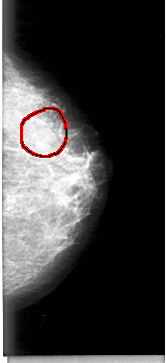

D_4025_1.RIGHT_MLO

FILE: D_4025_1.LEFT_MLO.OVERLAY

TOTAL_ABNORMALITIES 1

ABNORMALITY 1

LESION_TYPE MASS SHAPE LOBULATED MARGINS OBSCURED

ASSESSMENT 0

SUBTLETY 5

PATHOLOGY BENIGN

TOTAL_OUTLINES 1

BOUNDARY